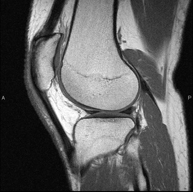

- RM Rodilla

Exploración para el estudio de lesiones en la articulación, como roturas meniscales y de ligamentos cruzados (unicamente detectables mediante esta prueba), condropatía o desgaste del cartílago y multitud de otras alteraciones derivadas de la actividad deportiva y los cambios degenerativos (osteoartrosis). Tiene una duración aproximada de 18 minutos. No emplea radiación ionizante.